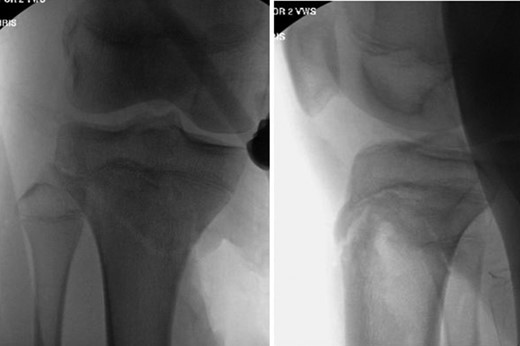

Patient is a 14-year-old male who slipped and fell while jumping off of a diving board and landed onto a flexed right knee. The patient was stable on presentation and neurovascularly intact with the knee locked in flexion. Skin was tenting anteriorly over the tibial tubercle and his compartments were swollen but compressible. A single plain film view (Fig. 1) was obtained prior to orthopaedic consultation. Closed reduction under sedation and splitting was attempted in the ED with partial but unsatisfactory improvement. Post-reduction radiographs (Fig. 2) demonstrated a tibial tubercle fracture with extension through the entire proximal tibial physis with metaphyseal involvement posteromedially. We classified this as a type IV tibial tubercle fracture, Salter–Harris II variant. In conjunction with patient and family we planned for urgent closed versus open reduction and application of knee-spanning external fixator. Immediately prior to surgery in the pre-operative holding area, the patient noted increasing right leg pain. In the operating room (OR), a marked increase in swelling with tense skin was observed. Due to rapidly progressive swelling and nature of the fracture, the decision was made to proceed with a 4-compartment fasciotomy of the right leg. The medial-sided fasciotomy (Fig. 3) revealed significant bulging of the superficial and deep compartments; however, the anterior and lateral compartments were less swollen. The fracture was unable to be closed reduced intraoperatively, therefore proximal extension of the medial fasciotomy wound was performed to open and reduce the fracture under direct visualization. Anatomic reduction was achieved and a knee-spanning external fixator was applied (Fig. 4). Approximately 72 hours later the patient was brought back to the OR for irrigation and debridement, lateral wound closure, and medial wound vacuum placement. Another 72 hours later, he returned to the OR for removal of the external fixator, ORIF, and split-thickness skin grafting of the medial fasciotomy site. An anterolateral approach was used with a 3.5 mm proximal tibial locking plate (Fig. 5). At most recent follow-up (Fig. 6), six months post-op, the patient is pain free, ambulating without assistive device, and has returned to all desired activities.

Presenting plain film view demonstrating proximal tibia fracture.